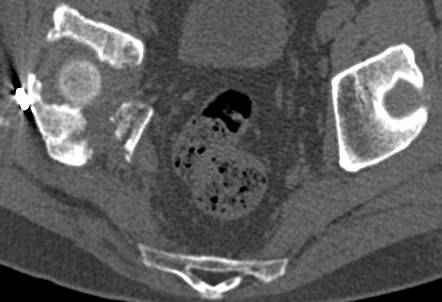

высылаю дополнительно сканы.

итак, второй вариант: высокий двухколонный с вовлечением КПС... Ни одно из основных повреждений не репонировано, кроме задней стенки. Скорее всего попытка реконструкции вертлуги сейчас будет очень травматичной и не очень эфективной, т.е. вероятный риск более значим, чем ожидаемая польза... Лучше подождать, и потом сразу эндопротез

подождать сколько, чего? такая дыра в задней колонне не закроется никогда.

потом эндопротез какой? в такой ситуации приходит на ум Burch-Schneider cage, в 35 лет, дальше что делать?